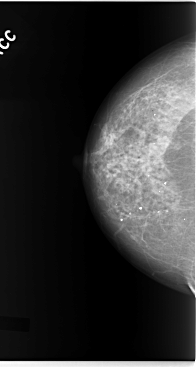

C_0093_1.RIGHT_MLO

RIGHT_MLO LINES 5880 PIXELS_PER_LINE 3096 BITS_PER_PIXEL 12 RESOLUTION 50 NON_OVERLAY